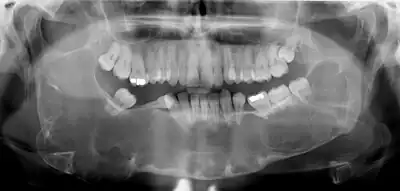

Radiographs of odontogenic keratocysts show well-defined radiolucent areas with rounded or scalloped margins which are well demarcated.[12] These areas can be multilocular or unilocular. The growth pattern of the lesion is very characteristic from which a diagnosis can be made as there is growth and spread both forward and backward along the medullary cavity with little expansion. No resorption of teeth or inferior dental canal and minimal displacement of teeth is seen. Due to lack of expansion of the odontogenic keratocyst, the lesion can be very large when radiographically discovered.[9]